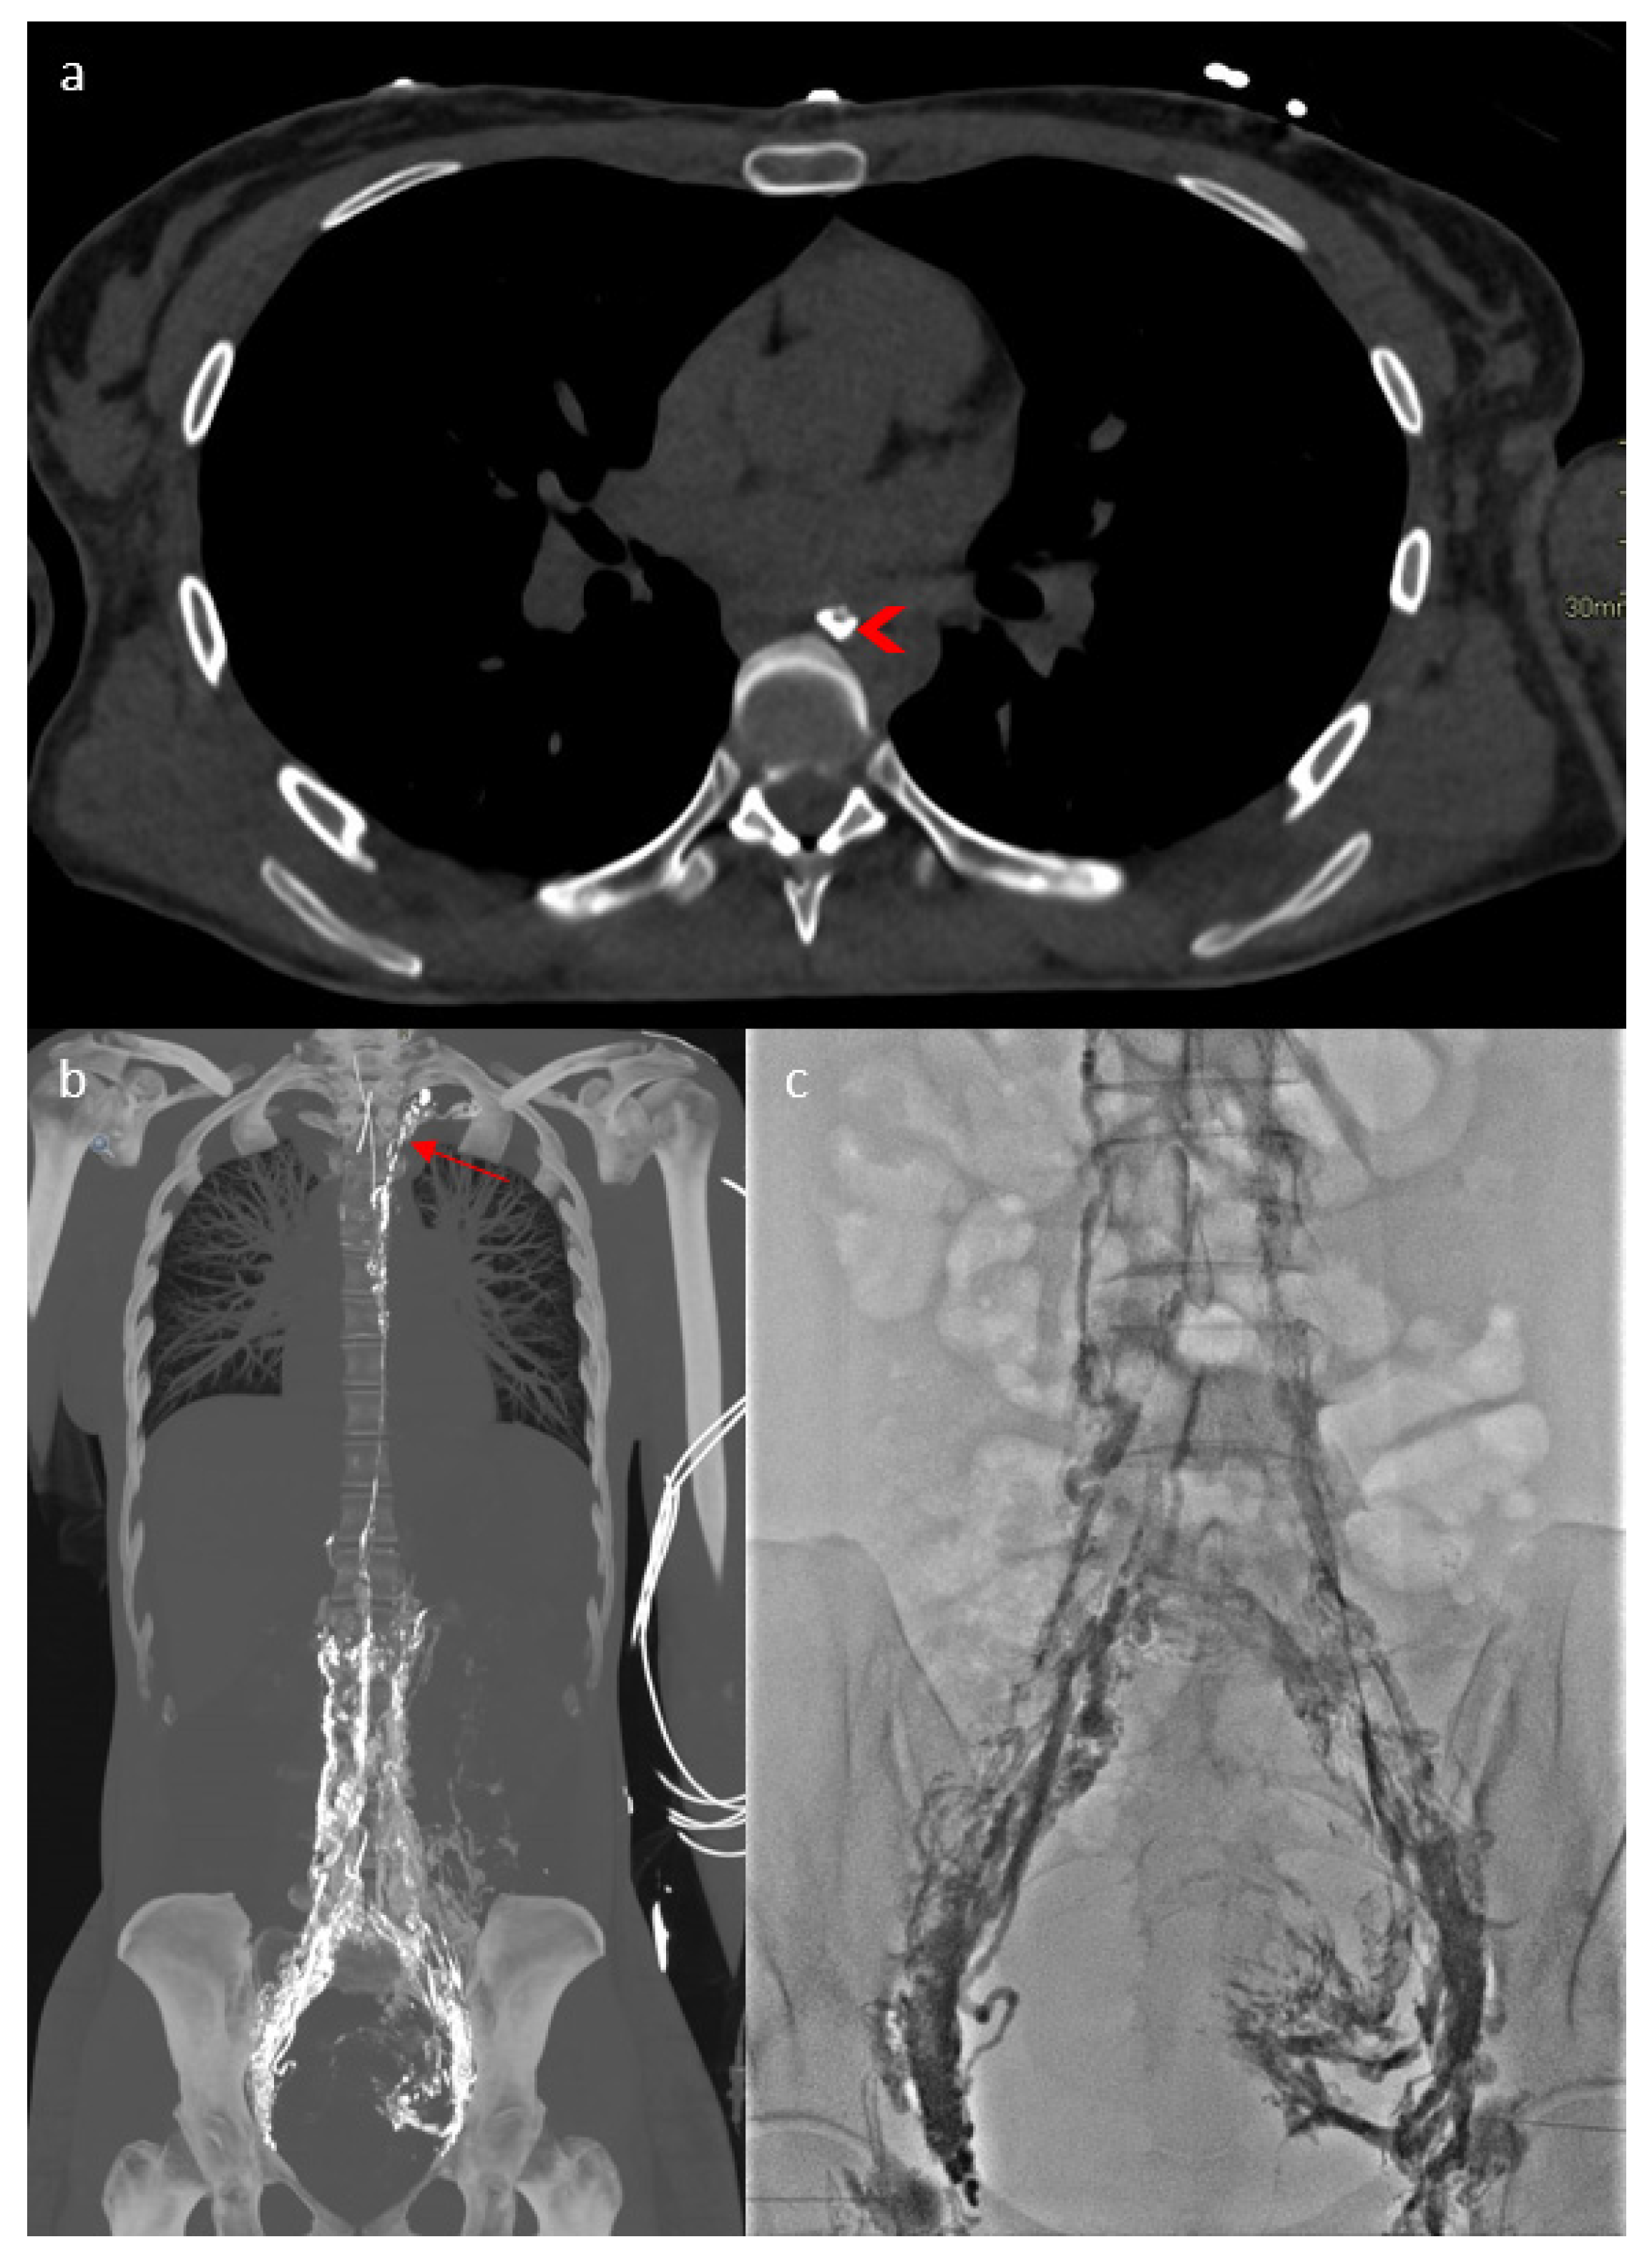

2. Case Report

3.1. Case Discussion and Physiopathological Hypothesis